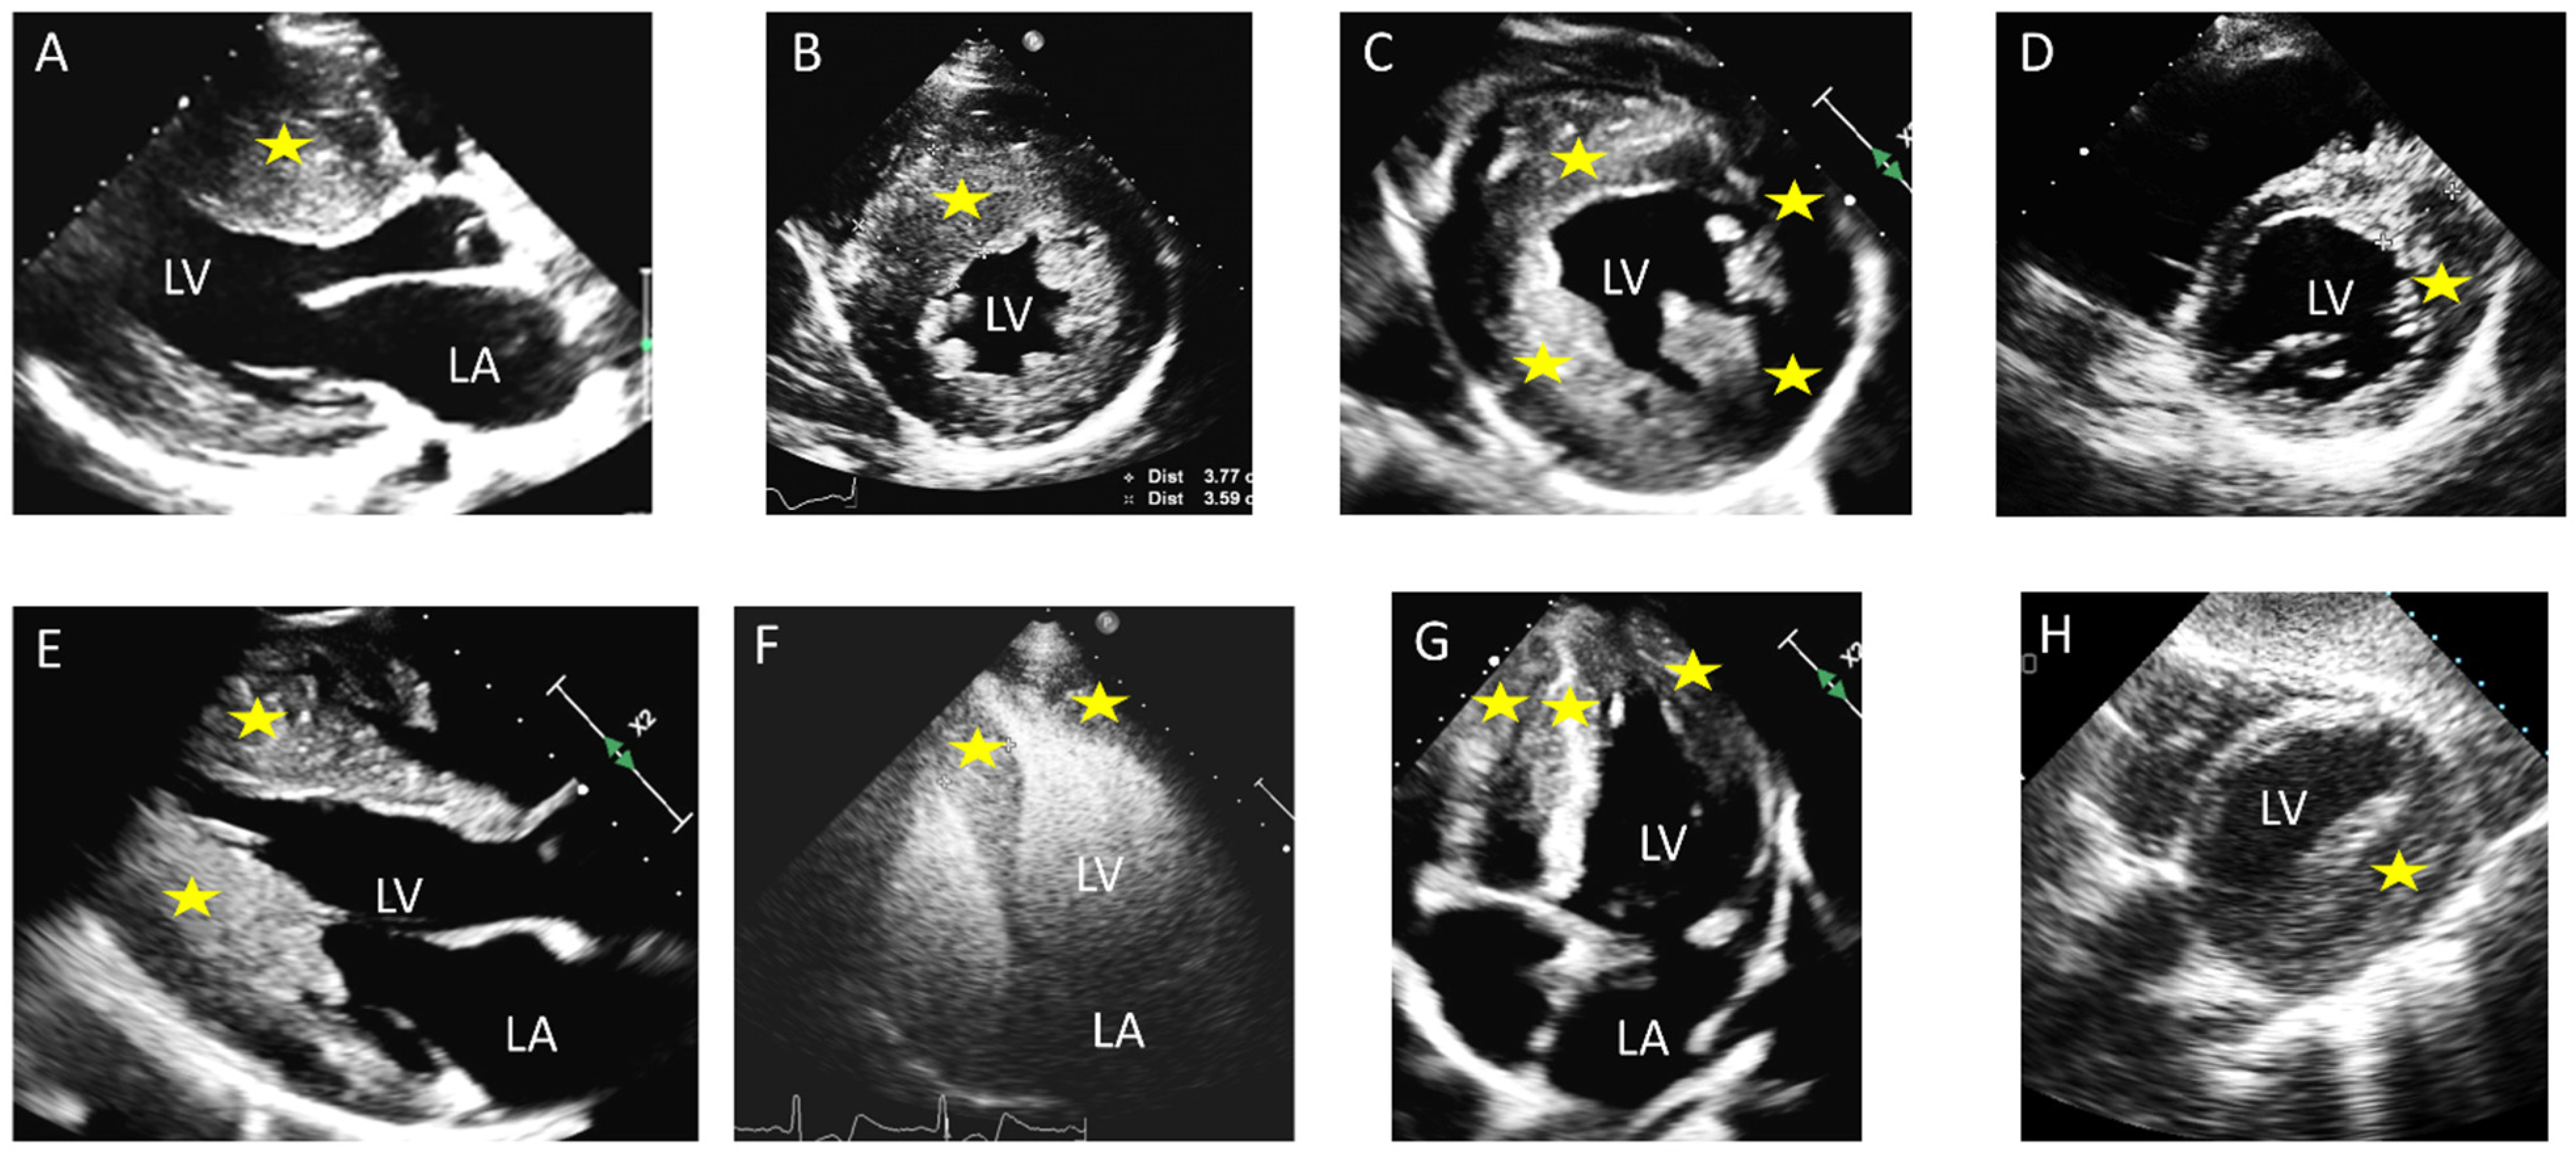

| Echocardiography | Septal hypertrophy; LVOT obstruction; SAM of the anterior mitral leaflet ± SAM-associated mitral regurgitation | Uniform thickening of LV walls; no LVOT obstruction typically | Apical wall thickening; “ace-of-spades” morphology of the LV cavity; ±apical aneurysm |

| CMR Findings | Asymmetric septal hypertrophy; LGE at RV insertion points and patchy LGE at the site of maximum hypertrophy | Symmetrical hypertrophy with variable patterns of LGE | Apical cavity systolic obliteration, loss of apical tapering; an apical aneurysm ± apical LGE and/or thrombus may be present |

| Clinical Manifestations | Syncope (especially if obstructive), exertional dyspnea, chest pain, palpitations, SCD | Often asymptomatic or mild symptoms; SCD risk depends on extent of fibrosis | Chest pain, palpitations; SCD less common; apical thrombosis may cause symptoms due to systemic embolization |